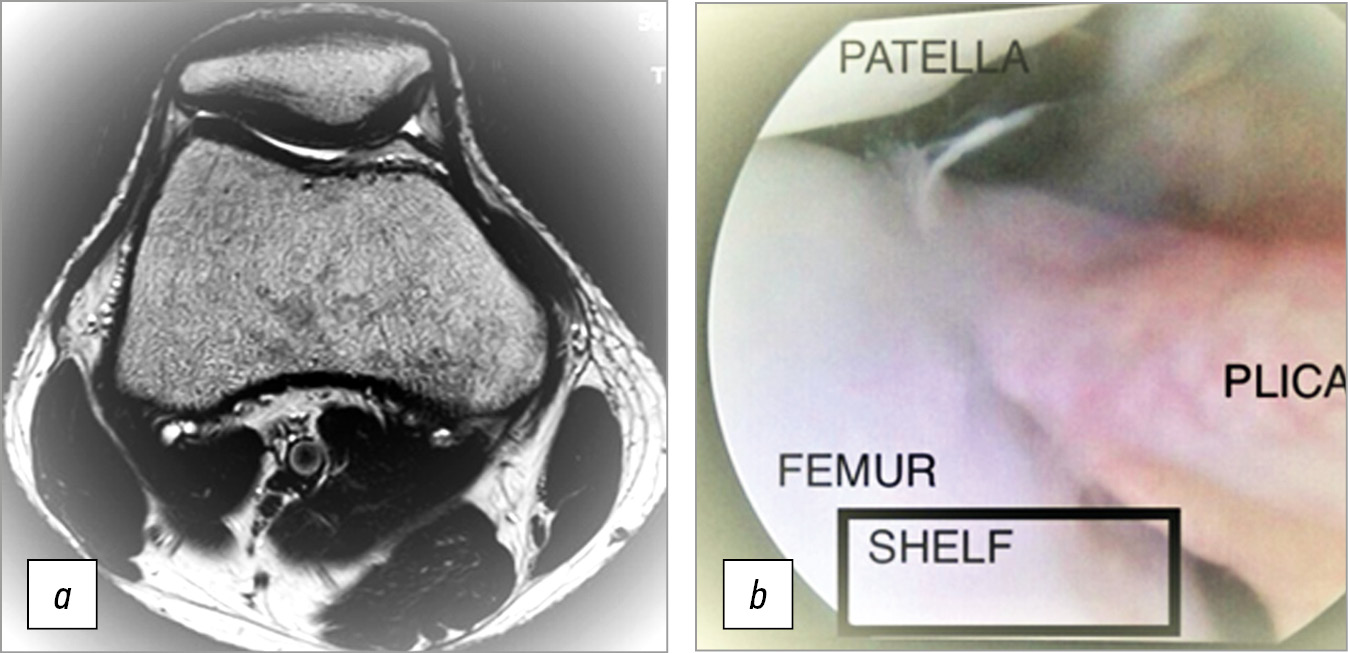

- тип D — складка распространяется на область медиального мыщелка бедренной кости, утолщена, неровная, имеет центральный дефект (фенестрированная складка) (рис. 2).

Рис. 2. На магнитно-резонансной томограмме (a) (аксиальные срезы Т2ВИ) обнаружена толстая, фиброзированная медиопателлярная синовиальная складка типа D, частично покрывающая медиальный мыщелок бедренной кости с развитием Shelf-синдрома, и повреждение хряща медиальной фасетки надколенника, на артроскопии (b) обнаружено полное соответствие с данными магнитно-резонансной томографии

Fig. 2. Magnetic resonance imaging (a) (axial slices of T2VI) revealed a thick, fibrosed medial patellar synovial fold of type D, partially covering the medial femoral condyle with the development of Shelf syndrome, and medial patellar facet cartilage damage; arthroscopy (b) correlated with magnetic resonance imaging data